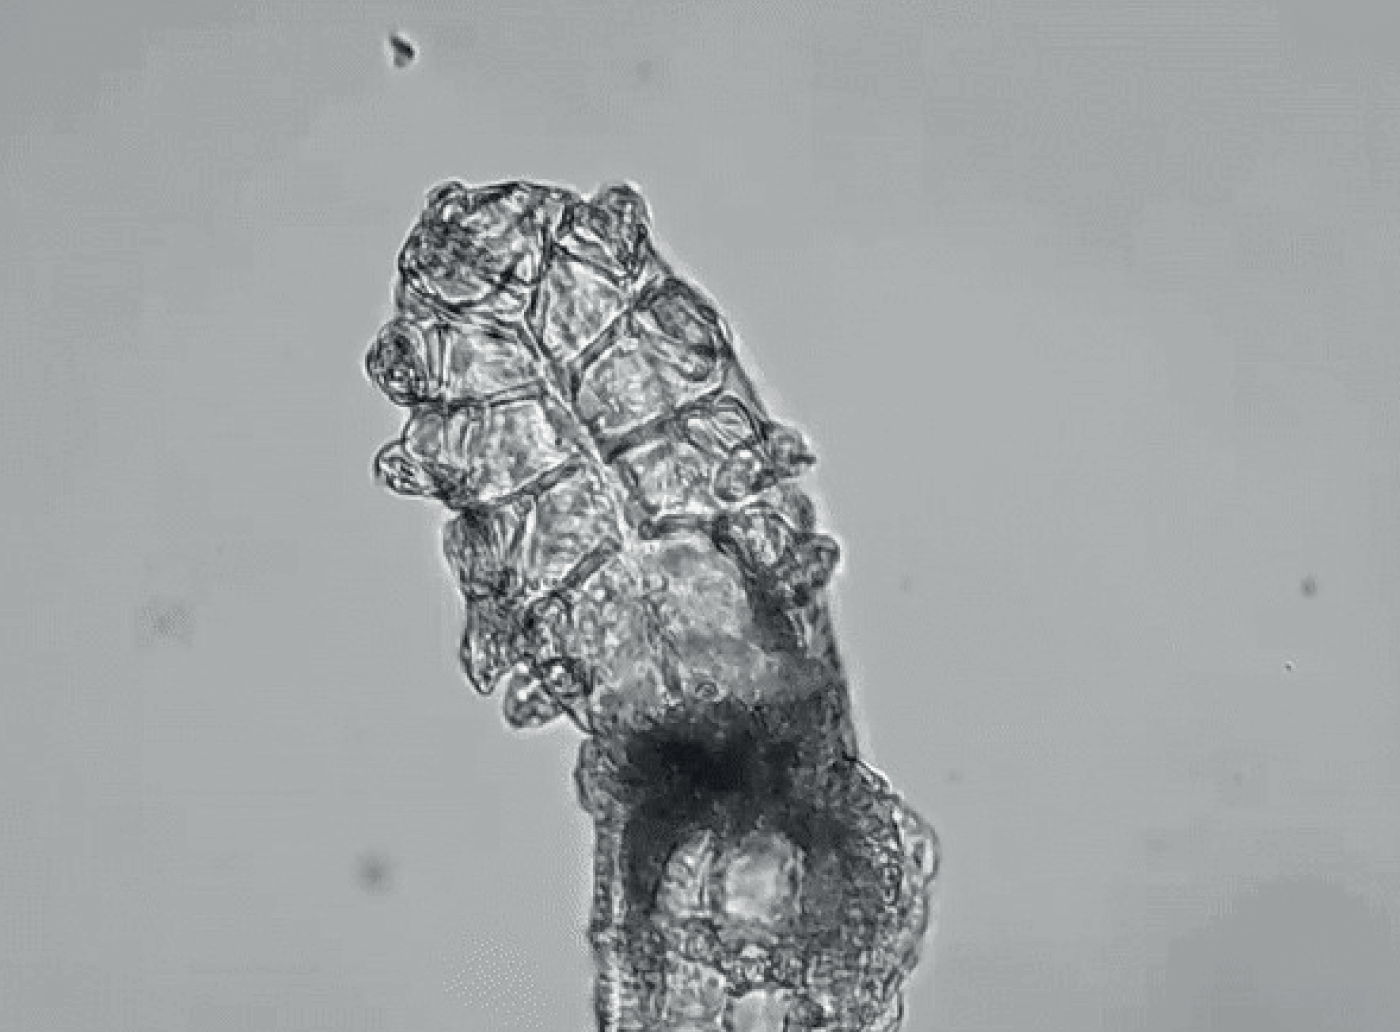

Demodex folliculorum: larger species of Demodex mite that burrows into eyelash follicles.

Demodex brevis: smaller species of Demodex mite that inhabits the sebaceous and meibomian glands.

Demodex mites are the most common ectoparasites found on humans. There are two species of Demodex – D. folliculorum and D. brevis – that live on the skin of the face and eyelids. The former burrows into eyelash follicles, whereas the latter inhabits the sebaceous and meibomian glands (4, 5). Although Demodex mites are common in low numbers, an overpopulation or infestation of mites, also called demodicosis, is associated with blepharitis (6). Demodex infestation increases with age (3,7, 8, 9), present in 84 percent of patients 60 and older and in nearly all patients by the time they reach 70 (8).

Demodex mites contribute to blepharitis inflammation via mechanical, chemical, and bacterial mechanisms (5). The overcrowded mites scrape the epithelial cell lining with their claws and lay eggs in the follicle, causing follicular distention, misdirected lashes, madarosis, and irritation. Mites also excrete digestive enzymes as they feed and exude waste when they die, which causes inflammation, hyperemia, irritation, and epithelial hyperplasia. Lastly, bacteria living on the mite surface or in its gut cause inflammation of the surrounding ocular tissues. As the mites proliferate in this nutrient-rich environment, the partially digested epithelial cells, waste, and eggs form collarettes (or “cylindrical dandruff”) at the base of the lashes. These collarettes are now recognized as pathognomonic for Demodex blepharitis (9, 11).